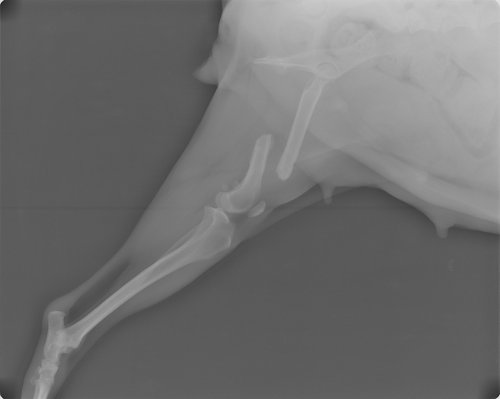

Tilly wurde am 19.2.2013 kastriert und da haben wir nochmal ein Kontrollröntgen machen lassen. Auf diesem Foto kann man sehr gut erkennen, dass der Knochen kürzer ist.

Am 30.9.2013 hat Tilly die Platte an ihrem Oberschenkel wieder rausbekommen. Es geht ihr gut und sie hüpft schon wieder rum. Die OP hat 130 Euro gekostet.